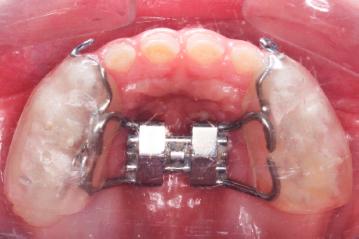

An acrylic cap type expansion appliance was prepared using the Leone A2620 expansion screw (Leone Orthodontic Products, Sesto Fiorentino, Florence, Italy) for each group. Hooks were added distal to the lateral incisors. After occlusal adjustments, the RME appliance was bonded using a glass ionomer cement (Multi-cure Glass ionomer/3M™-Unitek™-Monrovia, USA). The RME appliance was applied to the deciduous teeth of 5 patients (3 males and 2 females) between the ages of 4 and 7, as their permanent molars had not yet erupted. The families were instructed to activate the screw two quarter turns a day (2 × ¼ turn = 0.5 mm), every morning and every evening for the first 10 days. In patients who did not need expansion, activation was still performed for 10 days to ensure suture mobilisation. In cases in which further expansion was required, RME activation was continued until the necessary amount of expansion was achieved (Figure 2). Mid-palatal sutural opening was not monitored radiologically, but midline diastema formation or widening was observed in all children. An expansion of 10.8 ± 2.4 days was carried out on average for the 4–7 age group and 10.8 ± 1.8 days on average for the 8–11 age group.

Acrylic Cap Splint Rapid Maxillary Expansion Appliance.